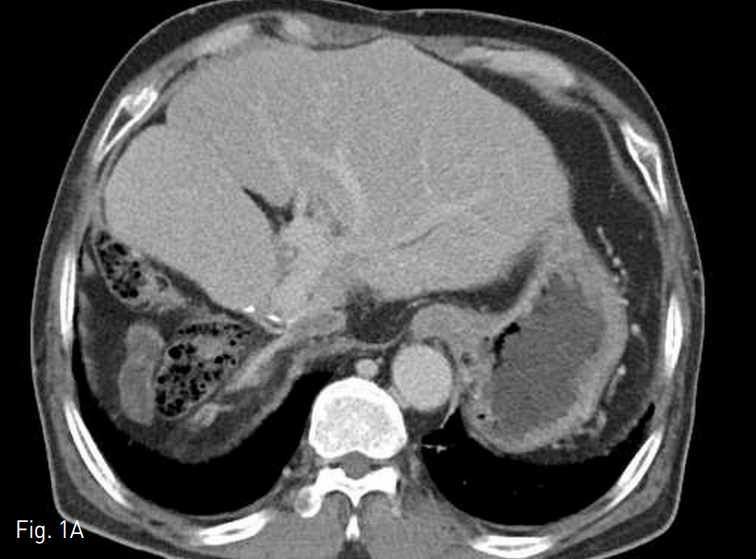

Fig. 5

A. 22 mm x 6 cm stent was inserted in IVC graft.

B. Follow up venography shows improved blood flow and disappeared collateral circulations.

찌그러져 있던 하대정맥 이식편에는 6 mm x 4 cm balloon catheter (Mustang, Boston Scientific, Natick, MA, USA)를 사용하여 확장시켰고, 22 mm x 6 cm stent graft (S&G, Sung-nam, Korea)를 위치시킨 후 14 mm x 4 cm balloon (Mustang, Boston Scientific, Natick, MA, USA)으로 최대한 확장시켰다. 마지막으로 시행한 정맥조영술에서 혈류가 개선되었으며, 측부 순환들도 보이지 않았다 (Fig. 5).